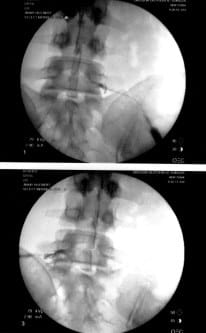

And this time there's pictures! (Click on the image for more detail and pictures from the scene of the crime with circles and arrows and a paragraph on the back of each one to be used as evidence against... Oops, never mind. The red arrows point to the inserted needles.)

The picture above is from the procedure, where they stick a needle down in my spinal column, about 3 inches, into in the epidural space where he injected a “nerve block” and some cortisone steroid stuff, which will reduce the inflammation and hopefully solve my problem of not being able to carry the weight of my body on my own two feet from time to time. Either that or figure out something else, but this is the first step (after trying medication and physical therapy - the first invasive step, you could call it).